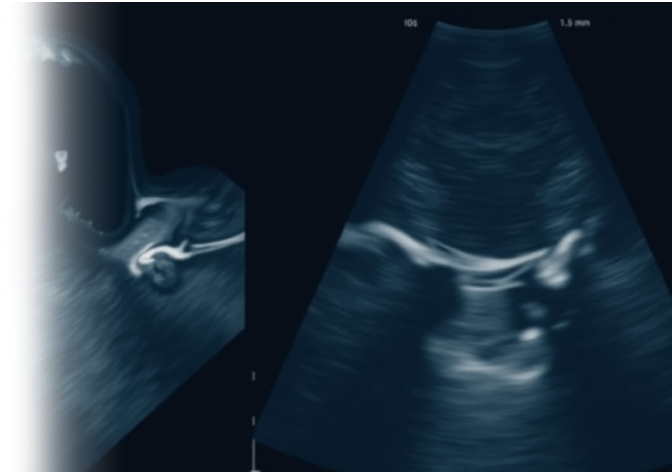

УЗИ щитовидной железы – важный метод исследования, позволяющий оценить различные патологии щитовидной железы. При проведении УЗИ оцениваются такие показатели, как расположение, форма, размеры, контуры, анатомическое строение, структура и эхогенность, а также выявляются признаки опухолевых и неопухолевых поражений. Дополнительно оценивается сосудистый рисунок и влияние окружающих тканей на состояние щитовидной железы.

Само исследование проводится с помощью ультразвукового аппарата, который передает звуковые волны через ткани и получает обратное отражение от органов.